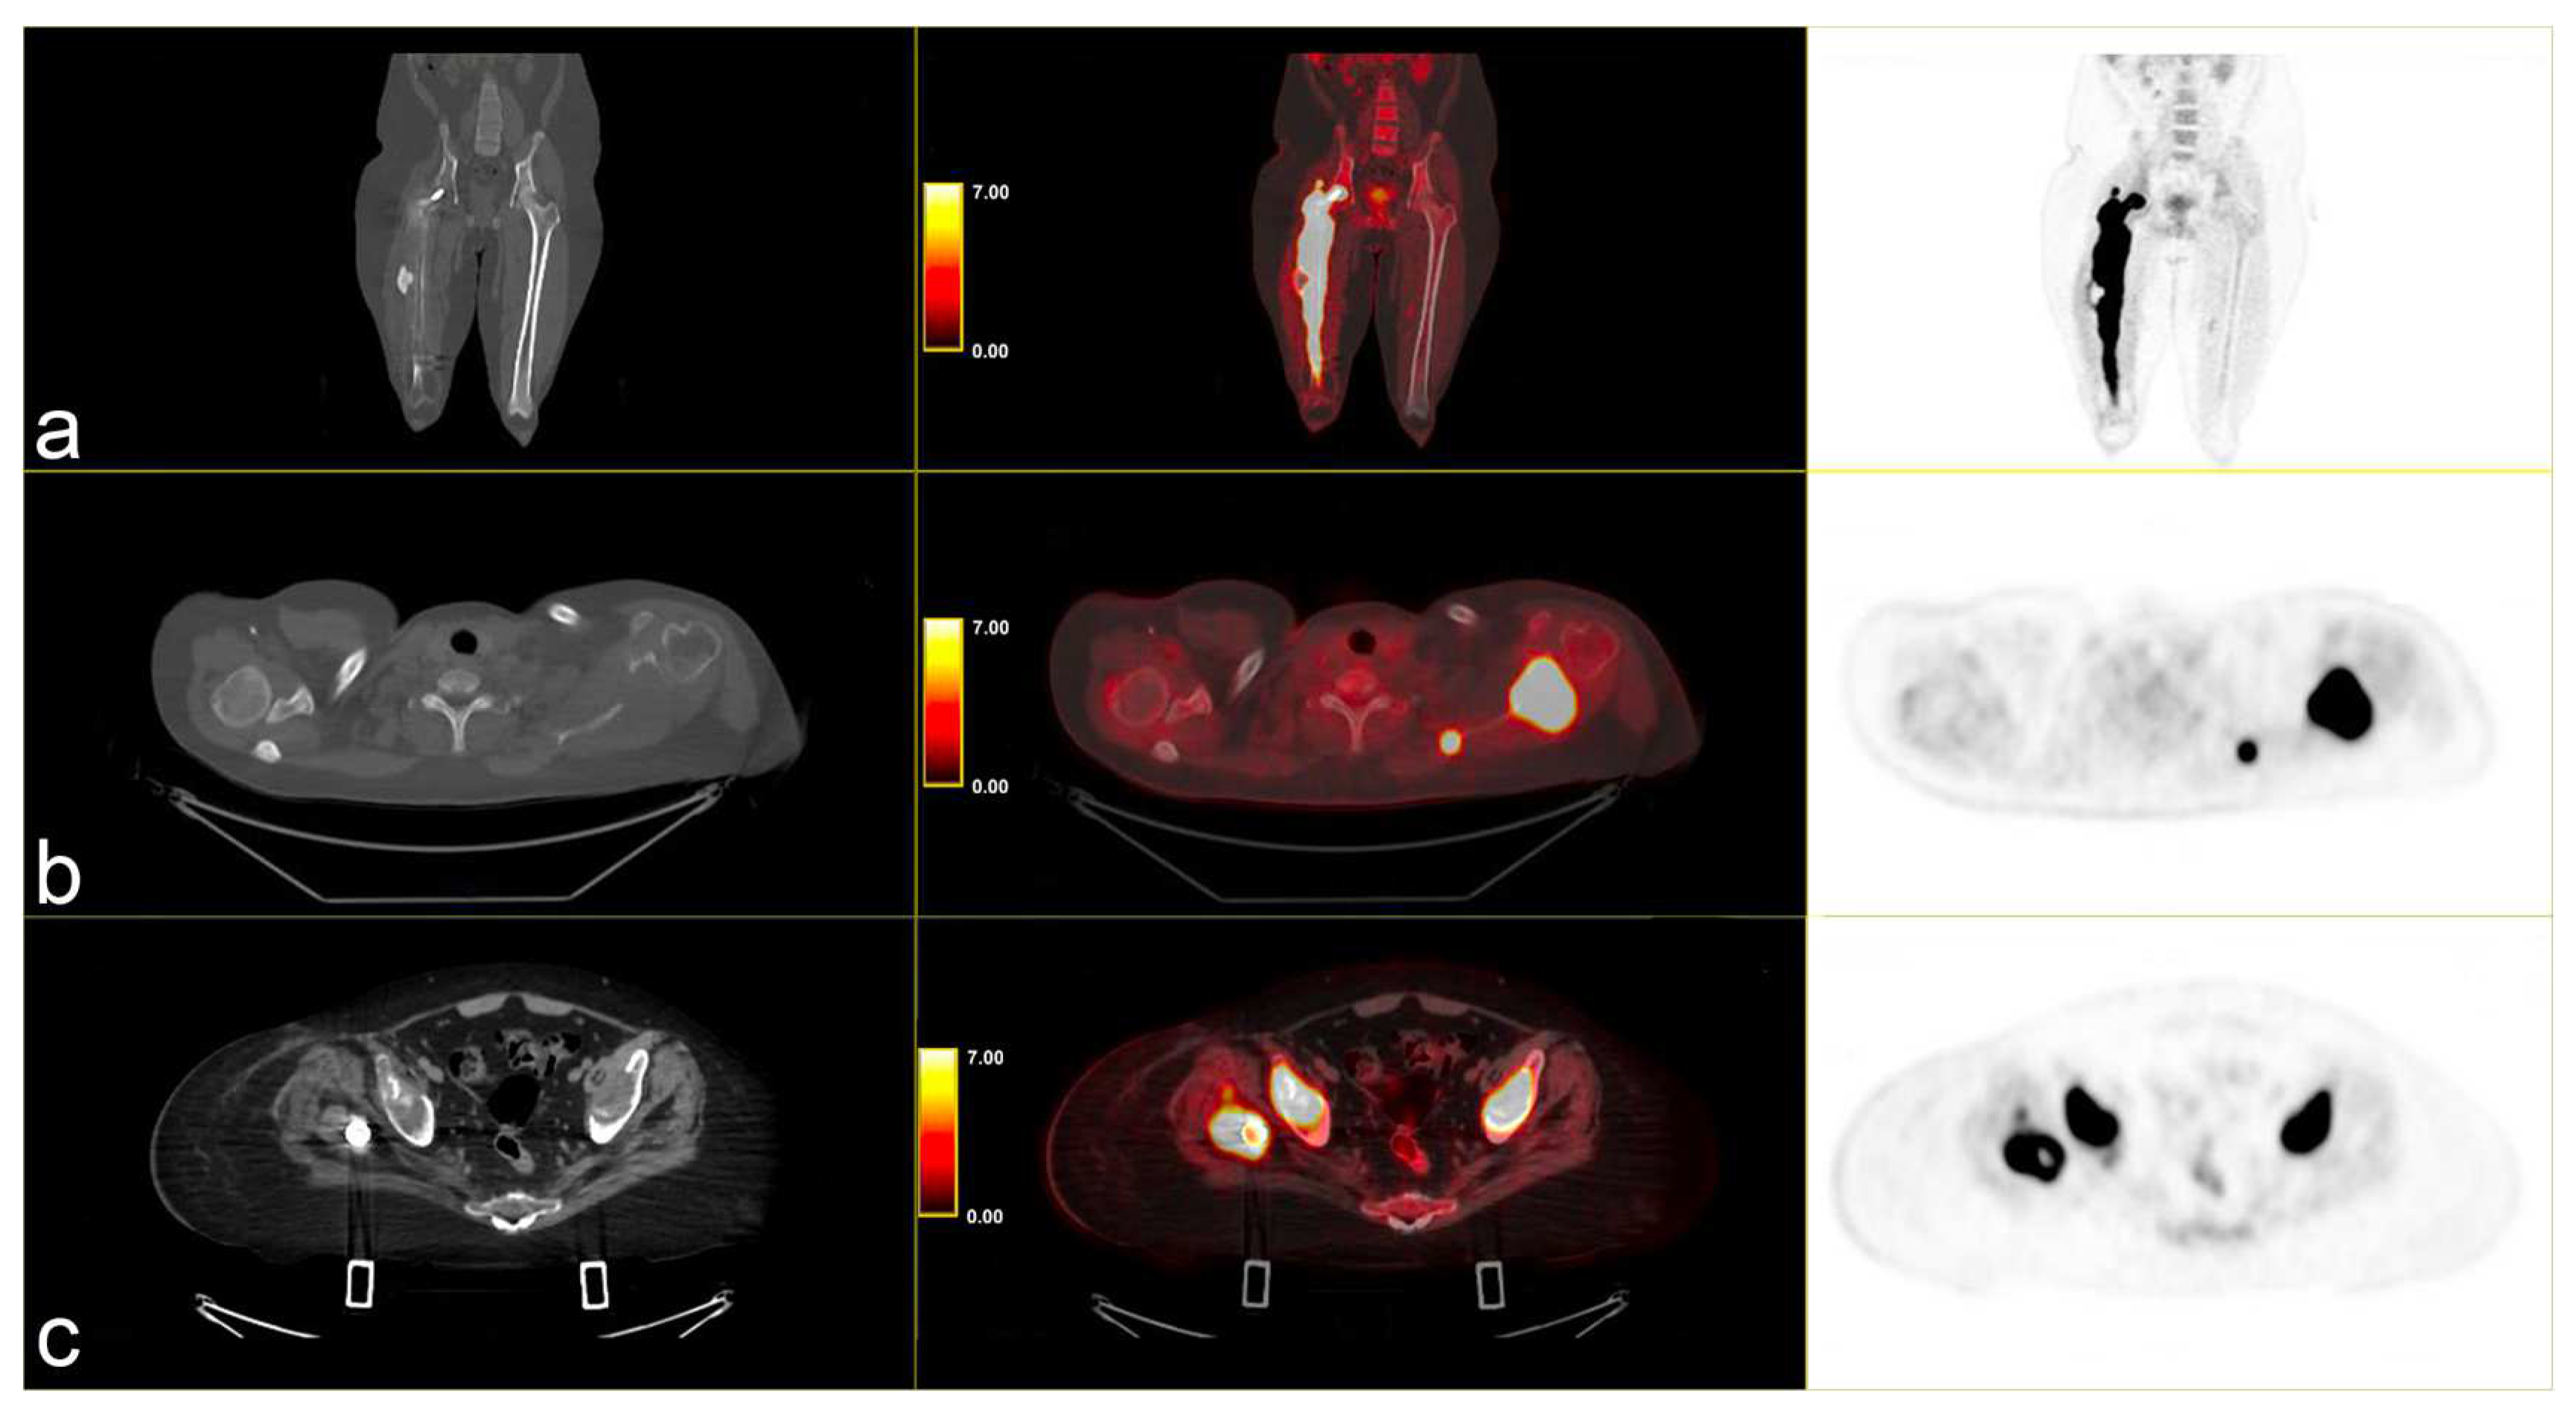

Following instrumental and clinical disease progression, the patient was treated with Sirolimus (an m-TOR inhibitor). At the first re-evaluation, instrumental progressive disease (PD) was observed with a moderate increase in bone SUVmax, particularly in the left scapula (SUVmax 34.8 vs. 31), and by the appearance of new lesions, such as the right iliac wing, numerous pulmonary nodules (SUV max 6) and lymph nodes in the left axilla (SUVmax 6.1) [Figure 3].

Figure 3.

PET/CT fused images show large hypermetabolic lesions in (a) the right femur, (b) the left scapula (with erosion of the cortical part), (c) thickened osteogenic lesions in the pelvis and bilateral iliac wings (thickened osteogenic lesions in with lower SUVmax: 6.7). From left to right CT PET/CT fused images and PET images.